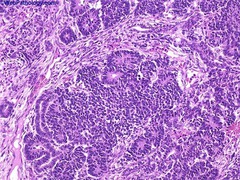

Vulvar Carcinoma

Malignant, arising from SQUAMOUS epithelium...very RARE Presentation: leukoplakia (must be distinguished from lichen) HPV type - HPV 16/18 - arises from vulvular intraepithelial neoplasia (VIN) = dysplasia (high N:C, hyper chromatic, pleomorphic, mitotic) - often reproductive age Non-HPV type - arising from lichen sclerosis - elderly women